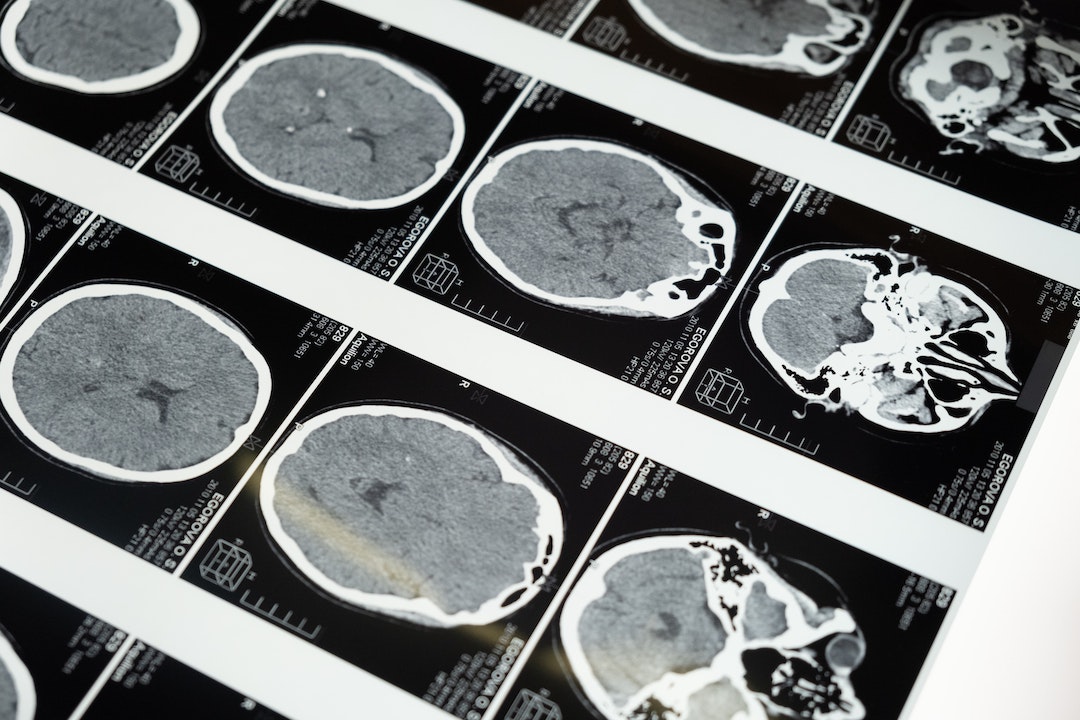

The basic premise of his work involves taking scans of the brain, and comparing the results to known healthy models. He then prescribes a mixture of nutritional, behavioural and medicinal strategies to treat the individual. Before and after scans are used to assess the treatment. His clinics have amassed the biggest global database of neuropsychiatric functional brain scans.

Dr. Amen started his medical career as an infantry medic and later developed a passion for medical imaging after training as an X-ray technician. His clinics rely on the innovative technology offered by SPECT Brain Scans to visualize the blood flow and activity of the brain. More than three decades of clinical research has supported the development of an immense brain-behaviour and imaging database with patients from 93 countries.

Developed in the 1970’s SPECT has been used to evaluate brain health, and specifically look for damage and trauma. It is routinely used to visualize the progress of disease states like Alzheimer’s and is used in the treatment of head trauma, chemical exposure, drug toxicity and neurological inflammation. Over 14,000 peer reviewed studies or articles have been published using published wither using or investigating SPECT Brain Scans.

Brain SPECT is a nuclear medicinal study that affords an inside view of the brain. Specifically it identifies:

Patterns of activity are used to understand what’s going on and can indicate various disease states:

For example patients with major depression can have exceptionally low brain activity, or exceptionally high – which should be taken into consideration when planning treatment. A personalized approach to healing individual brains, not symptom clusters is therefore critical. Dr. Amen’s team found that mild traumatic brain injury was a significant cause of psychiatric illness that was simply not being spotted using current methods. Behavioural issues, like temper problems, and mood disorders including anxiety, depression were frequently linked to previous physical trauma. Even insomnia was found to have physiological roots.